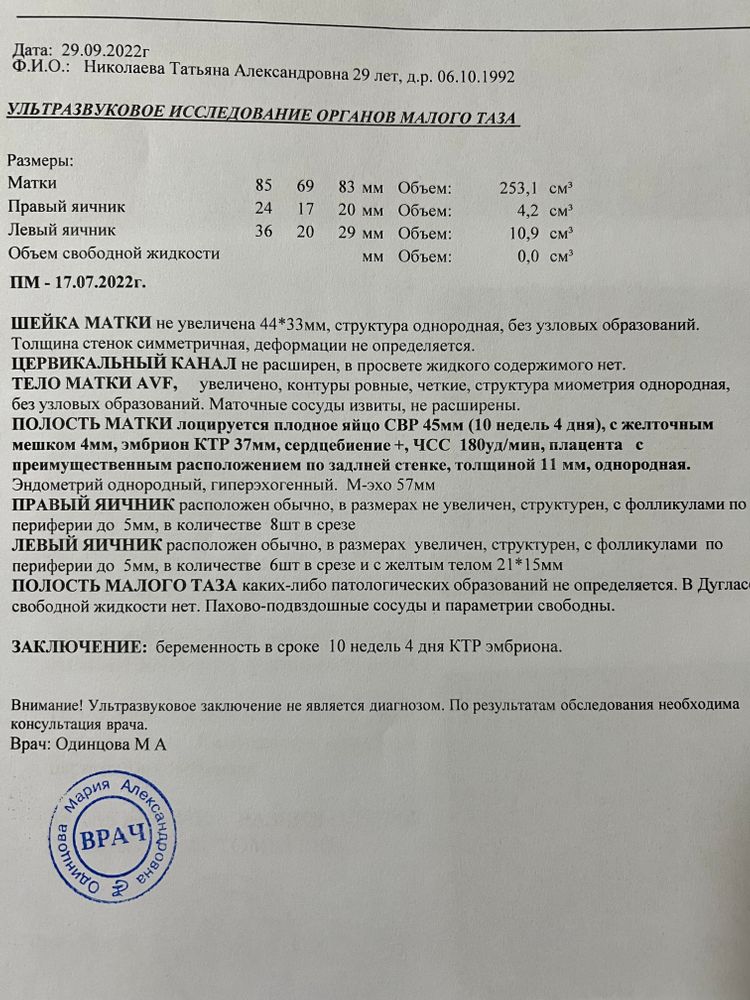

Но я этим постом не про переживания хочу сказать, а о своей радости, о моей маленькой тайне, о моем малыше, что тихонько притаился внутри меня. Он такой хрупкий и от зачатия ему всего 58 дней, но он уже поражает меня своими стойкостью и жизнелюбием. Поверьте, мне уже есть чему у него поучиться. Он мой маленький супермен и я горжусь им. Несмотря на все тяготы и волнения прошедшей недели он отлично вырос, умеет кувыркаться и вообще «очень активный товарищ» (это со слов врача узи). И хотя я пришла сделать узи только лишь с целью убедиться, что всё хорошо, врач по своей инициативе показала мне «третью ножку» и сказала, что это 100% мальчик. Я не сильно удивилась, потому что видела во сне моего сына (звучит как из области фантастики, но это факт) и вообще просто чувствовала, что у нас будет сын. После узи плакала с перерывами несколько часов, настолько это чудо кажется мне невероятным. Во мне растет человек, будущий мужчина! Вот такая я сентиментальная стала в беременность, а также плаксивая, тревожная. Гормональный фон ли, происходящие события так влияют, но до беременности я себя ощущала стойким оловянным солдатиком. Кто прочитал всем спасибо.